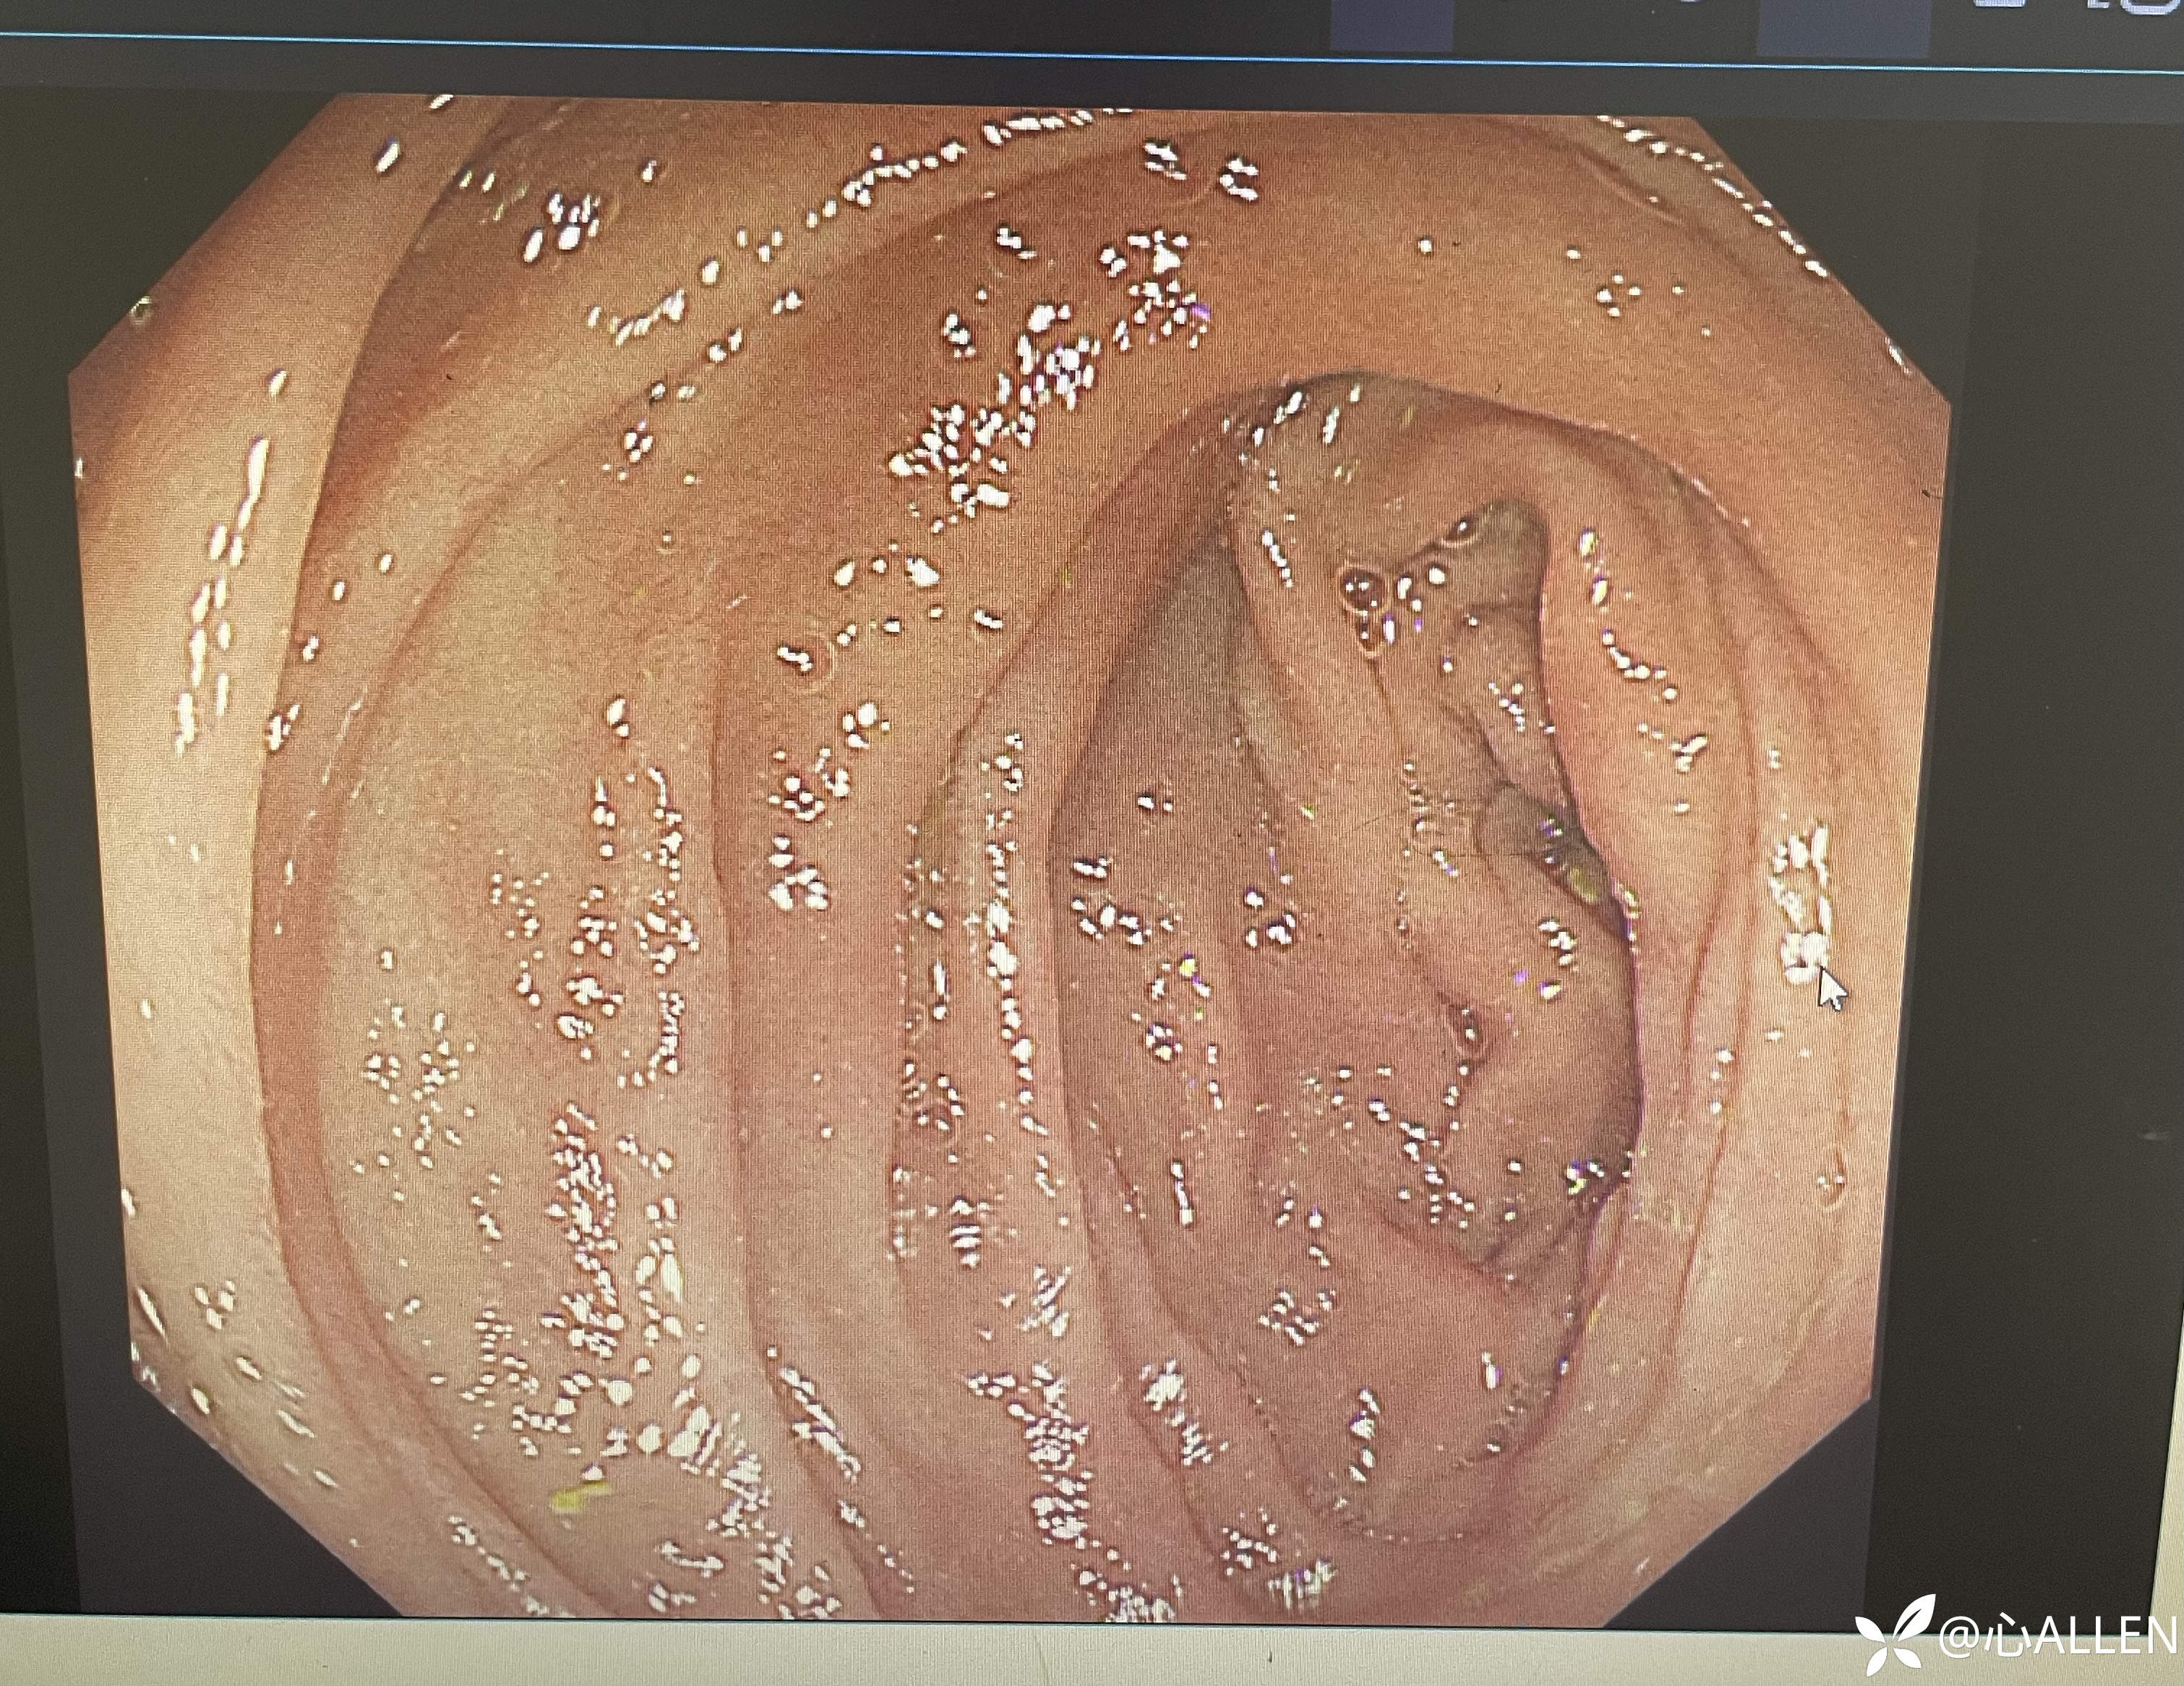

退镜至幽门口端,从倒镜发现的肠腔进镜观察

退镜观察球部吻合口

患者自诉出生后进食后恶心呕吐,遂行手术治疗,根据内镜图片推测患者手术方式及儿时疾病